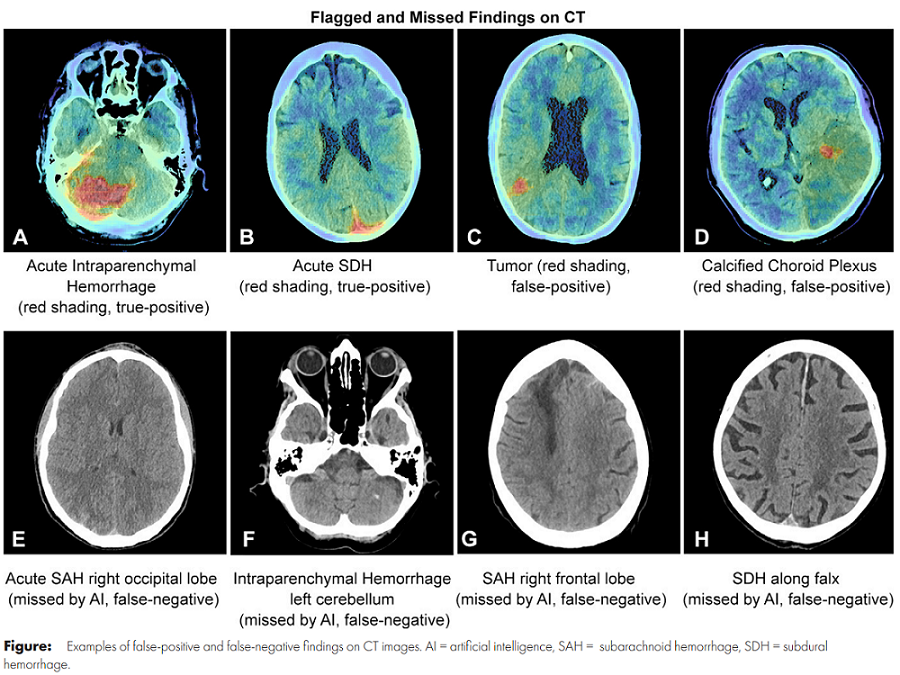

The AI showed high accuracy at detecting intraventricular hemorrhages (100%), but not so much for subarachnoid hemorrhage or subdural hemorrhage (70-80%). With a degree of low specificity, the AI may give a false sense of security. Implementation of the AI also expedited the time it took to rule out ICH – from 205 minutes to 167 minutes, and thus shortened the turnaround time in the emergency department. The study observes that the diverse practices, false alarms, limitations of human-machine interoperability and more factors in different scenarios may have acted against the improved time efficiency, and emphasizes this as a reason for further integration of AI in the workplace and defining AI frameworks.